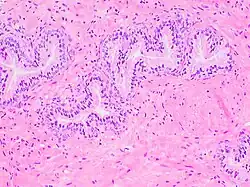

The prostate consists of glandular and connective tissue.[2] Tall column-shaped cells form the lining (the epithelium) of the glands.[2] These form one layer or may be pseudostratified.[4] The epithelium is highly variable and areas of low cuboidal or flat cells can also be present, with transitional epithelium in the outer regions of the longer ducts.[10] Basal cells surround the luminal epithelial cells in benign glands. The glands are formed as many follicles, which drain into canals and subsequently 12–20 main ducts, These in turn drain into the urethra as it passes through the prostate.[4] There are also a small amount of flat cells, which sit next to the basement membranes of glands, and act as stem cells.[2]

The connective tissue of the prostate is made up of fibrous tissue and smooth muscle.[2] The fibrous tissue separates the gland into lobules.[2] It also sits between the glands and is composed of randomly orientated smooth-muscle bundles that are continuous with the bladder.[11]

Over time, thickened secretions called corpora amylacea accumulate in the gland.[2]

Microscopic glands of the prostate -

Microanatomy of a prostatic gland, showing both luminal cells and surrounding basal cells. H&E stain. -